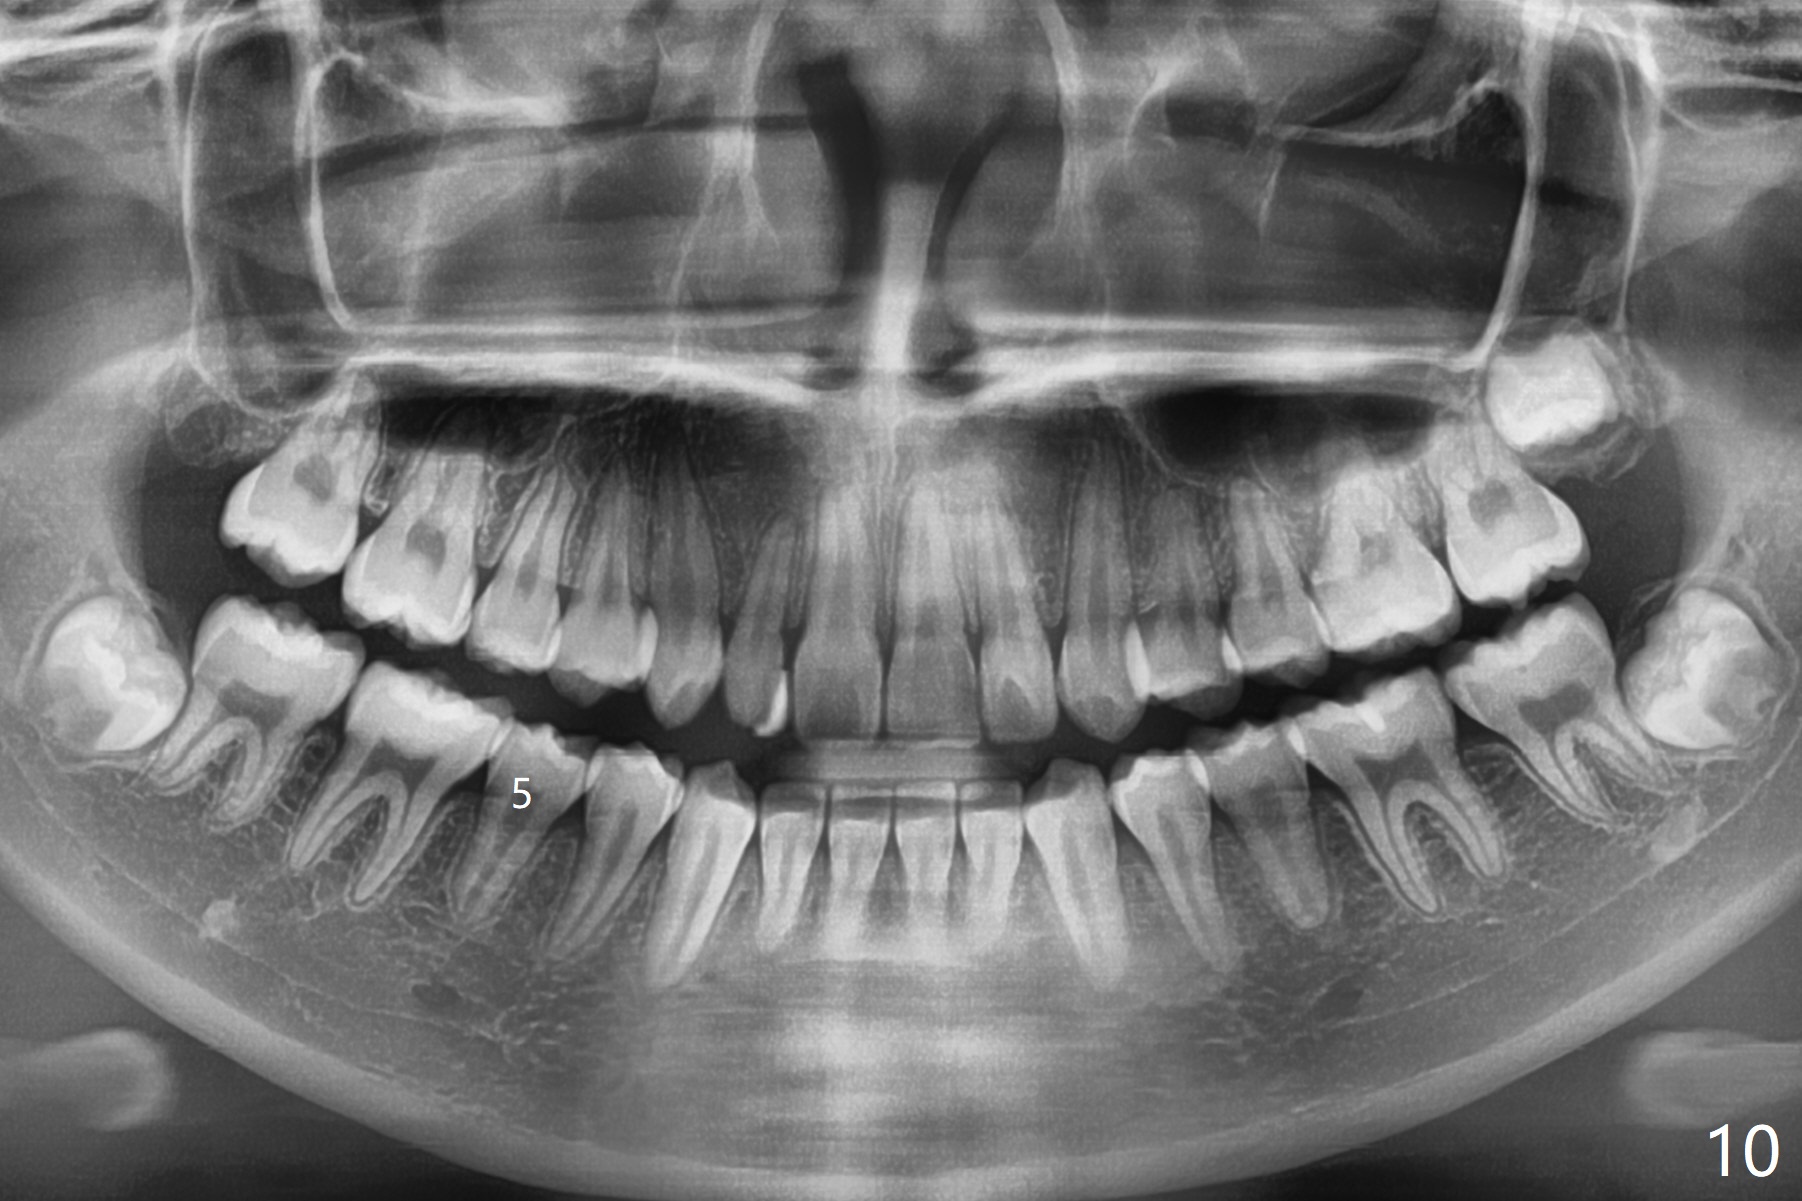

Nearly 6 months post banding (16x16 wires), LR5 has been overcorrected, while the upper dental midline appears to shift to the right (Fig.8). UL2 is going to be distalized (Fig.9). One months later, UL1 is to be distalized. Next appointment, check molar occlusion before any procedure. Panoramic X-ray taken 6 months post debanding shows no rotation at LR5 (Fig.10).